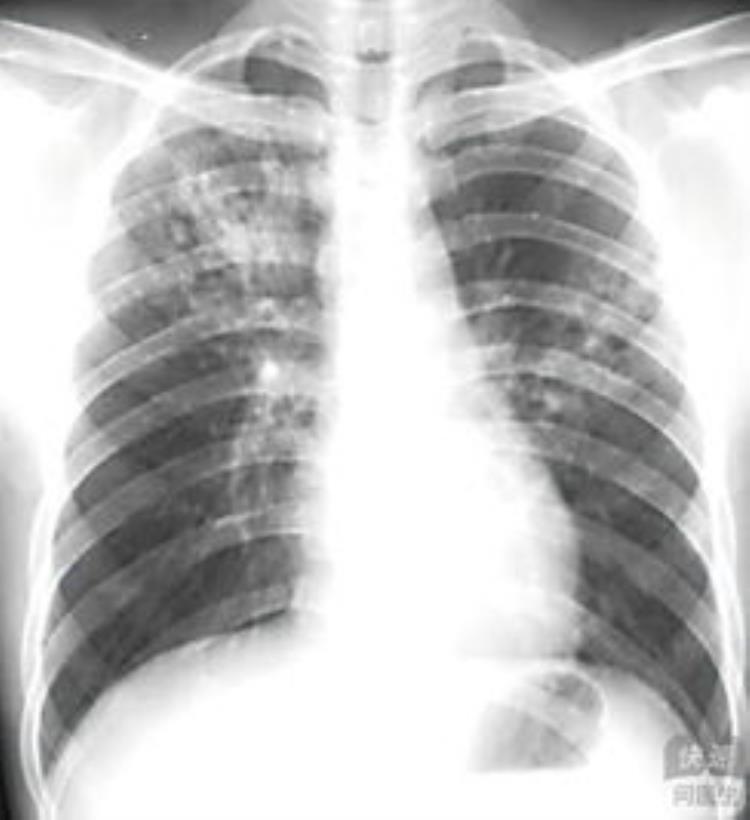

2.血行播散型肺结核:急性粟粒性肺结核,全肺均一结节(最严重)

X线:常规首选方法;

CT:病变细微特征的评价